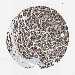

LIVER CANCER - Protein expressioni

A mouse-over function shows sample information and annotation data. Click on an image to view it in a full screen mode. Samples can be filtered based on level of antibody staining by selecting one or several of the following categories: high, medium, low and not detected. The assay and annotation is described here.

Note that samples used for immunohistochemistry by the Human Protein Atlas do not correspond to samples in the TCGA dataset.

Antibody stainingi

Antibody staining in the annotated cell types in the current human tissue is reported as not detected, low, medium, or high, based on conventional immunohistochemistry profiling in selected tissues. This score is based on the combination of the staining intensity and fraction of stained cells.

Each image is clickable and will lead to virtual microscopy that enables deeper exploration of all samples and also displays staining intensity scores, fraction scores and subcellular localization as well as patient and tissue information for each sample.

Antibody HPA012609

Antibody HPA012723

Antibody CAB011489

Staining

High

Medium

Low

Not detected

Intensity

Strong

Moderate

Weak

Negative

Quantity

>75%

75%-25%

<25%

None

Location

Nuclear

Cytoplasmic/membranous

Cytoplasmic/membranous,nuclear

Cholangiocarcinoma

Carcinoma, Hepatocellular, NOS